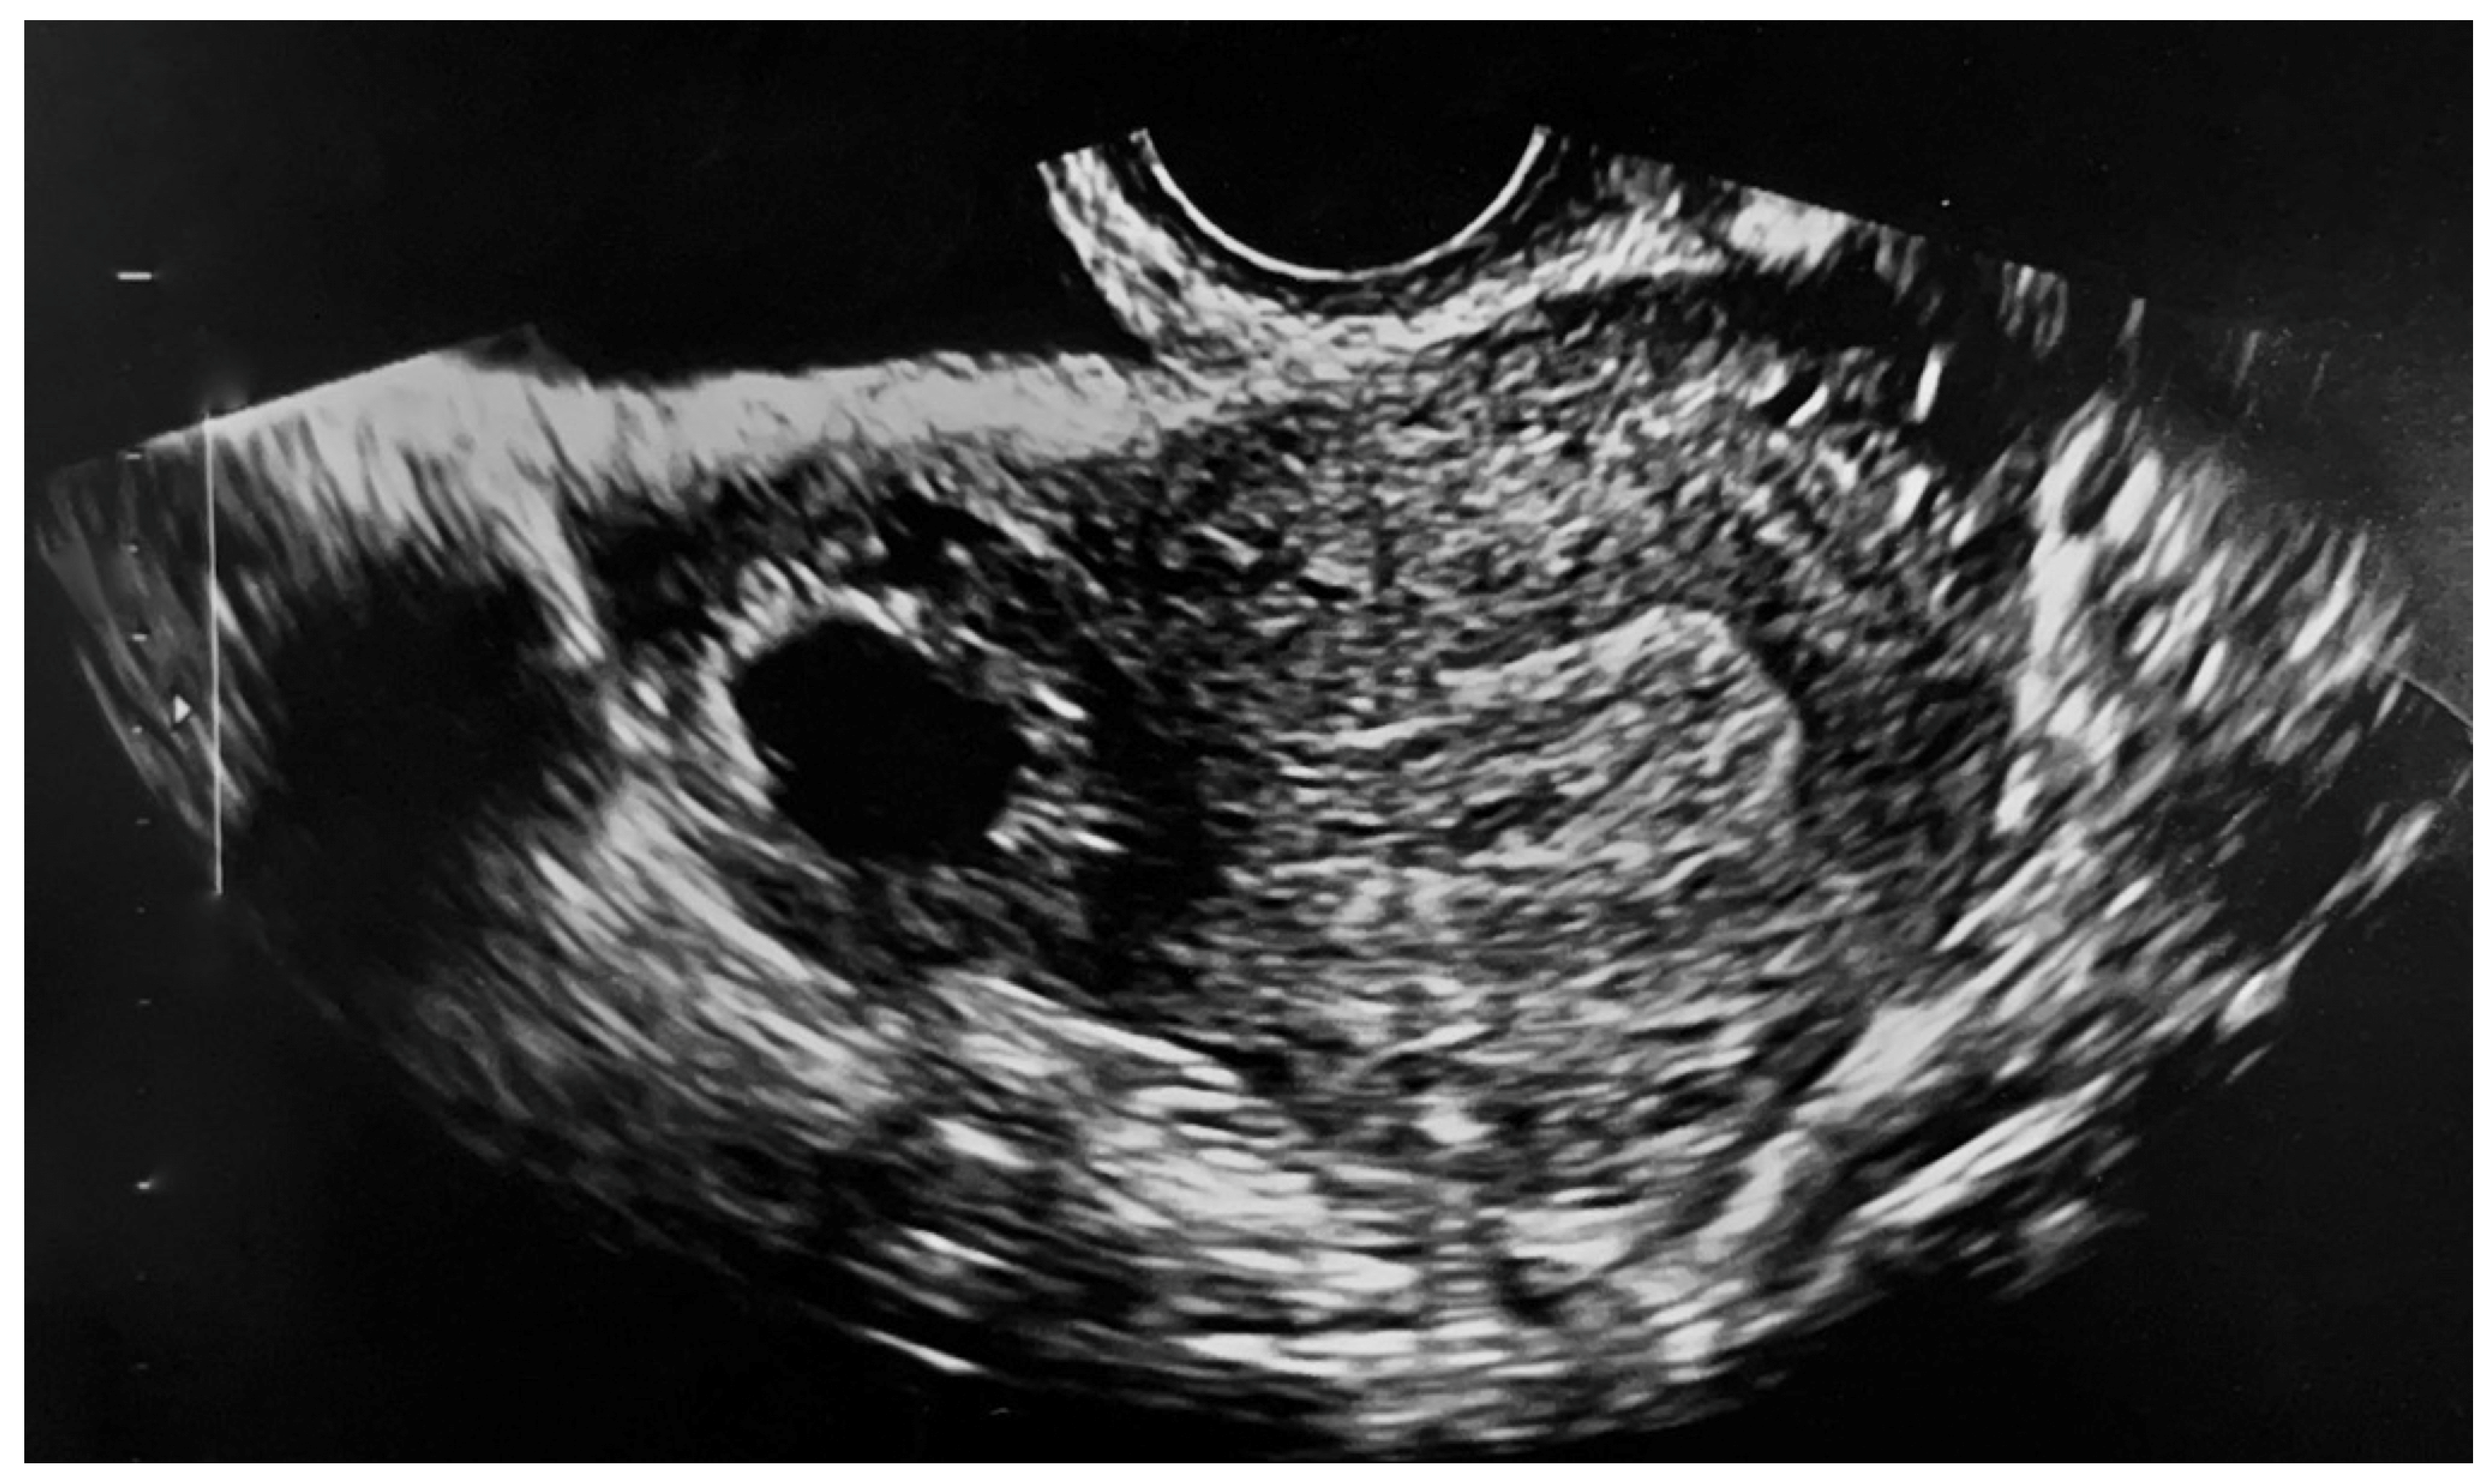

2. Case Presentation